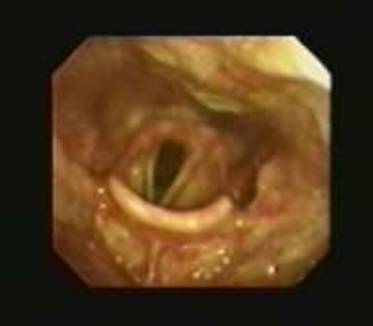

19 下图中所见的喉部是一个成年的

A. 男性

B.  女性

C.  马

19B

显示的喉头属于一个成年女性。 “声门裂”前方的三角形(声带之间中间的空间)清晰可见。一个男性的声带通常比女性的更厚,如果病人作深呼吸会注意到更外展,男性的声带开放更大(平均约有19毫米)。成年妇女的声门裂通常小于男性(一般女性的声门裂外展最大的直径为12毫米)。 声带随着呼吸移动,而位于上方的前庭皱襞不会。例如马,吸气时如果没有环杓展肌的作用,显著降低压力会引起喉的塌陷。在运动的时候,由于气流,持续久收缩这些肌肉把环杓软骨和声带拉伸,使喉头扩张。 一些马匹发育被称为喉返偏瘫。在这种情况下,环杓背肌麻痹导致环杓软骨受影响的一侧塌陷到喉头,在吸气时阻塞气道。顺便提一下,人类也有类似的发现!然而,不像马常常是遗传的,人常常由于肿瘤、感染、或外伤导致的。